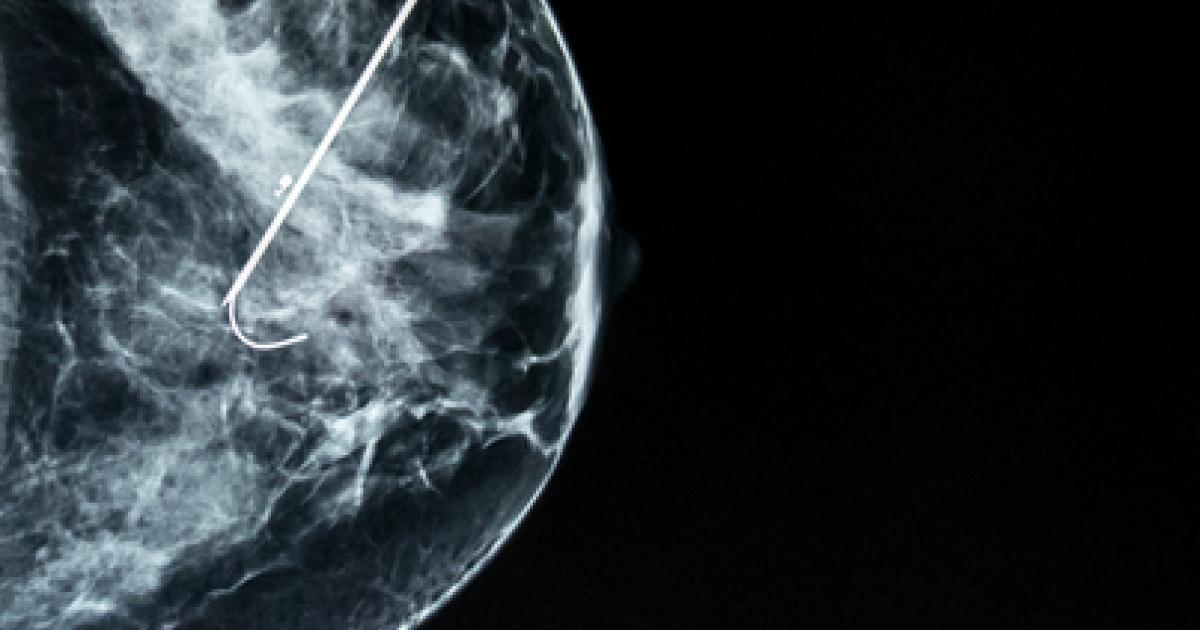

Caring for disease begins with diagnosis, you cannot treat a problem that is unknown to you. The diagnosis of breast cancer begins with identifying “a lump” whether detected by the patient or by screening mammography which detects more smaller lumps because it is more sensitive in finding the proverbial ‘needle in the haystack.’ Large lumps are easy to identify, no improvement is necessary. Because our science showed that as cancer got larger, it became ‘more aggressive,' we sought to find lumps earlier before the situation becomes more difficult or hopeless. Our ability to detect these smaller cancers increased over about eight years from 25.3 per thousand to 34.7 per thousand – about a 37% improvement [3]. In the words of the study’s author, “The change likely reflects improvements in mammography imaging technology, which permit the visualization of smaller lesions and greater detection of calcifications that result in increased cancer detection.” The underlying assumption was that earlier detection results in a better outcome and the measure of early was size. Therapy informed diagnosis and diagnosis responded. It wasn’t simply that size mattered, but for mammography, it was all that could be measured. Once identified, the lump biopsied, cancer confirmed and treatment initiated.

The treatment options were almost entirely surgical, with chemotherapy and radiation playing a supporting, adjunctive role. While ‘cure’ might be allusive, we found that early intervention resulted in improved survival, five and then ten-year cures. But for newer treatments, where chemotherapy or radiation was primary or sole treatment, our prior success necessitated a longer time-period to see better outcomes. Treatment changed at one rate, diagnosis at another, the dancers were out of sync. Another important treatment discovery was our failure to treat all small lumps successfully. Categorizing lumps by size was too heterogeneous for treatment. Size does not precisely identify biologic behavior. As best we can tell, that behavior is more closely associated with cancer's response to hormones. From treatment’s viewpoint, we now want to characterize cancers by their behavior; size is no longer the best measure. Those new criteria, because of the lag time brought by extended survival, was not established and shared for some time.

And that brings us to this current study. With the advantage of hindsight, the authors correlated the size of breast cancer at detection with the three markers we use to measure biological behavior, the grade (increasing abnormal appearance of the cells), and the response to estrogen and progesterone. This graph, from the study, captures the essence of their findings.

If you look across the categories of tumor size, the percentage of cancers with favorable biologic behavior decrease. Proof that size does matter. But when you look at the individual columns you see that size is heterogeneous regarding behavior. Some small tumors are biologically very aggressive (unfavorable in the chart) and others not so much. And the proportion of favorable tumors increases for patients over 40, the group of patients most likely to be diagnosed with cancer. The authors conclude, “Both tumor size and biologic features influence prognosis, but frequently a large favorable tumor can have a better prognosis than a small unfavorable tumor.” And nod to the future of diagnostic/prognostic factors, recognizing that “grade and receptor status are rather crude predictors of biologic features as compared with molecular assays.” Bottom line, size has lost its primary prognostic role, challenged by grade and hormone receptor status, measures that mammography cannot identify. All our effort in improving mammography to detect small has increased our difficulties [4] because our diagnostic tool is no longer dancing with our therapeutic considerations.